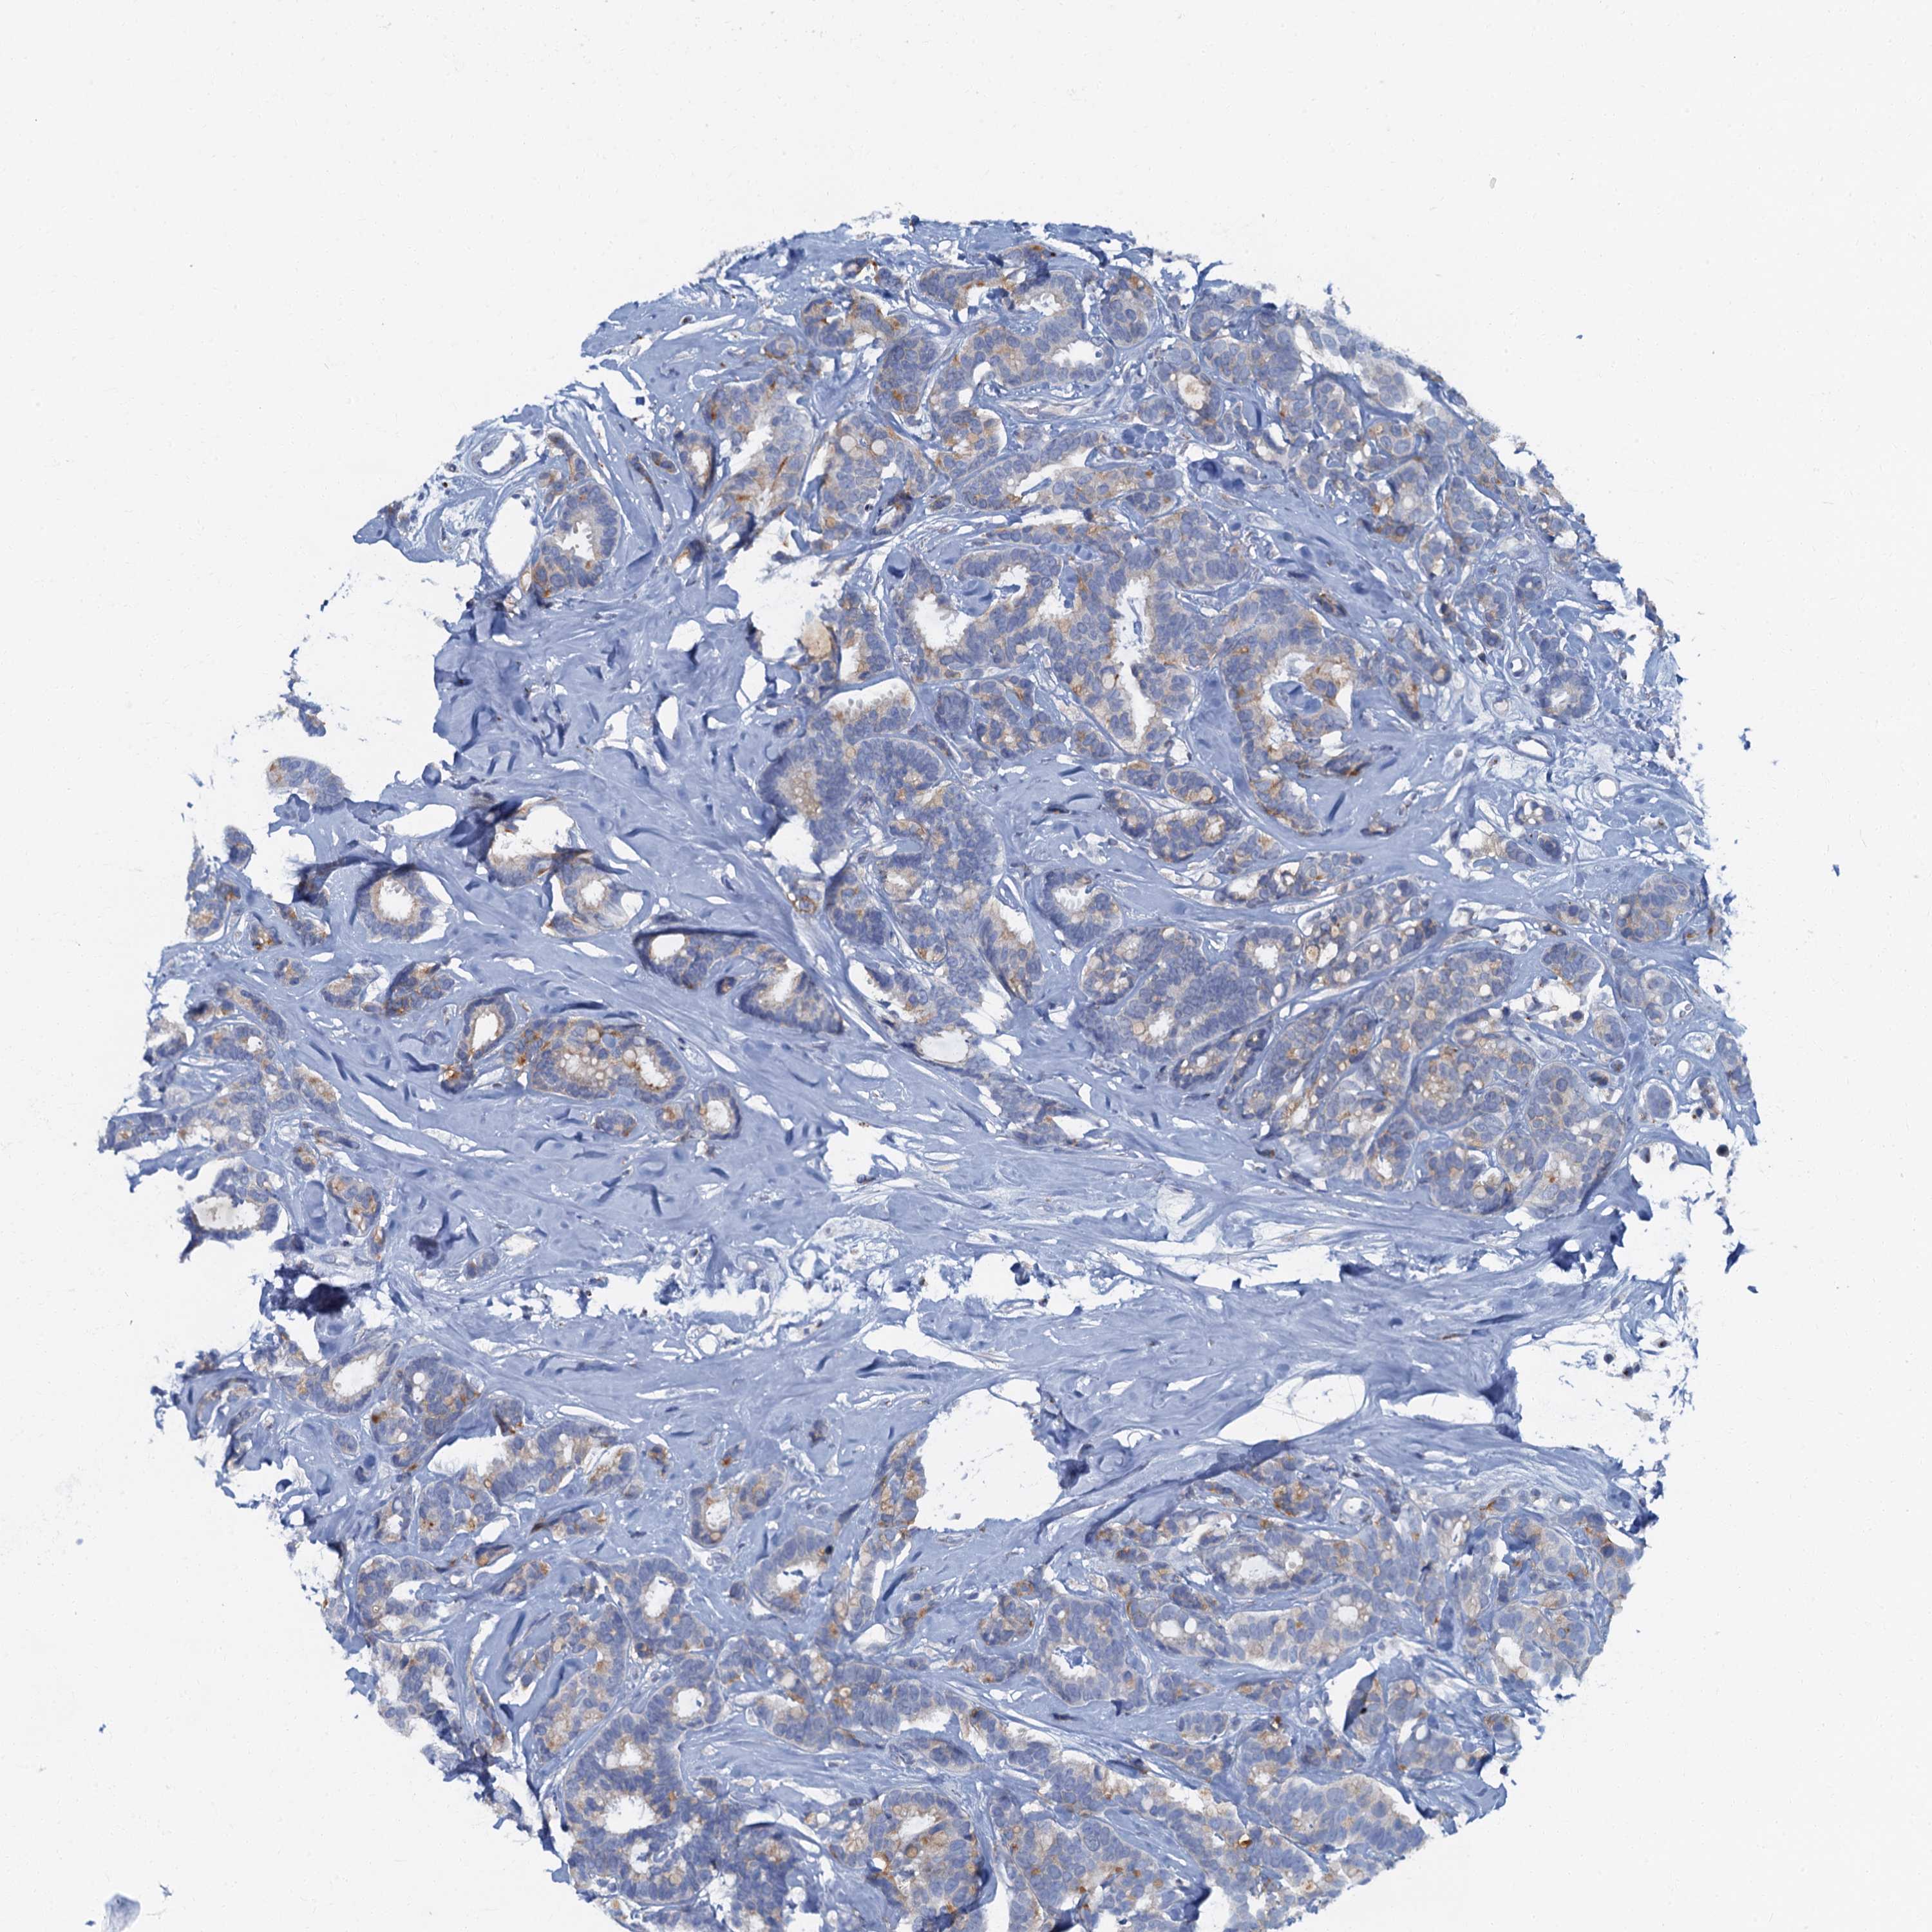

BRCA TCGA BRCA VALIDATION PROTEIN EXPRESSION